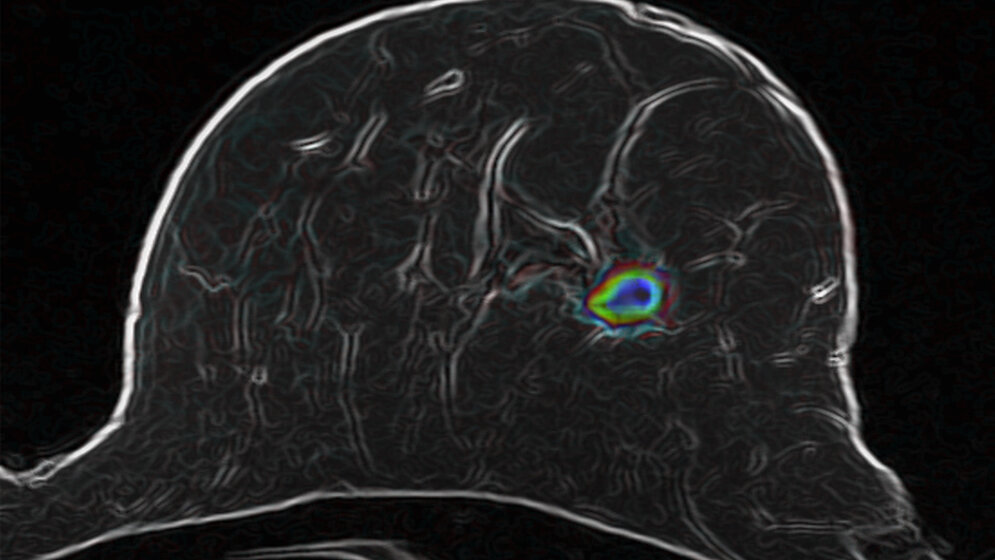

Der Radiologe hat sich daher gemeinsam mit seinen Kollegen daran gemacht, die diffusionsgewichtete Magnetresonanz-Tomographie (MRT) für die Untersuchung der weiblichen Brust zu optimieren und mit intelligenten computerbasierten Bildanalyseverfahren zu verbinden. Mit der diffusionsgewichteten MRT lässt sich die Bewegung der Wassermoleküle im Gewebe sichtbar machen und mit Hilfe eines Computeralgorithmus beobachten. Bösartige Tumoren verändern die Gewebestruktur, was sich auf die Bewegungsmuster der Wassermoleküle auswirkt.

Jetzt belegen die DKFZ-Wissenschaftler in einer von der Dietmar-Hopp-Stiftung geförderten Studie, dass die optimierte diffusionsgewichtete MRT in Kombination mit intelligenten Bildanalyseverfahren tatsächlich zuverlässige Aussagen über bösartige Veränderungen in der Brust erlaubt. Dazu untersuchten sie insgesamt 222 Frauen, die sich nach einem auffälligen Mammographiebefund einer Biopsie unterziehen sollten. Bevor die Gewebeprobe genommen wurde, analysierten die Forscher das Brustgewebe der Studienteilnehmerinnen mit ihrer neu entwickelten Methode.

Das vielversprechende Ergebnis: Die Zahl der falsch positiven Befunde ließ sich in der Studiengruppe um 70 Prozent reduzieren. Tatsächlich vorhandene bösartige Veränderungen konnten die Wissenschaftler in 60 von 61 Fällen erkennen. Das entspricht einer Trefferquote von 98 Prozent und ist vergleichbar mit der Zuverlässigkeit von MRT-Methoden, bei denen Kontrastmittel zum Einsatz kommen.